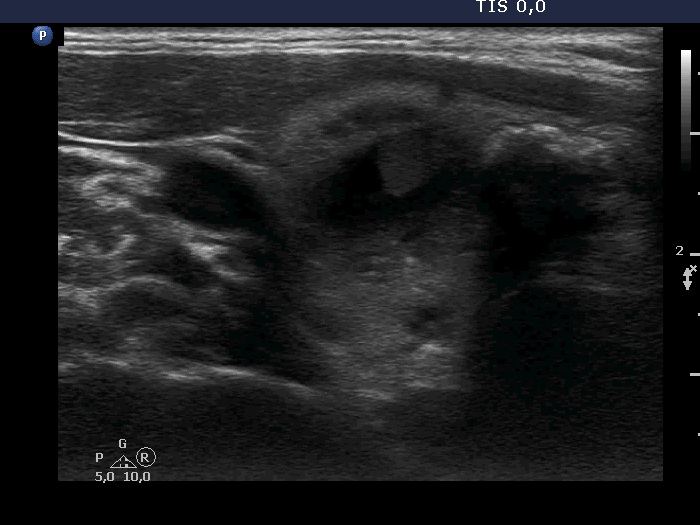

Ultrasonography. The thyroid was echonormal. There were two nodules in the right lobe, a dominantly cystic one, and a lesion in the lower third which had macrocalcifications. There was a minimally hypoechoic lesion in the left lobe which showed halo sign and perinodular vascularity. Compared with the first examination, the nodule in the left lobe showed a substantial increase, this time the dimensions were 15x14x17 mm.

The echogenicity of the solid part of a cystic nodule is significantly influenced by the location. In this case, the solid part was echonormal dorsal to the cystic content while moderately hypoechoic in the medial part. The difference in echogenicity is explained by the echo amplification dorsal to the fluid.

The echogenic figures are better to judge before aspiration. These were clearly back wall figures and comet-tail artifacts before the aspiration.